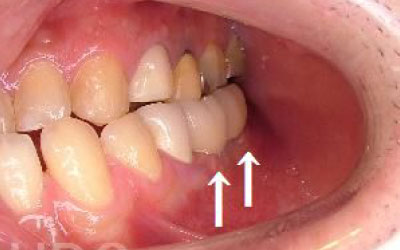

2 歯が傾いてくる、落ちてくる

歯は互いに支え合ってバランスを保っています。つまり、歯が抜けるとその支えがなくなり、抜けた部分の隣の歯が倒れたり、上の歯が下に沈んだりすることがあります。